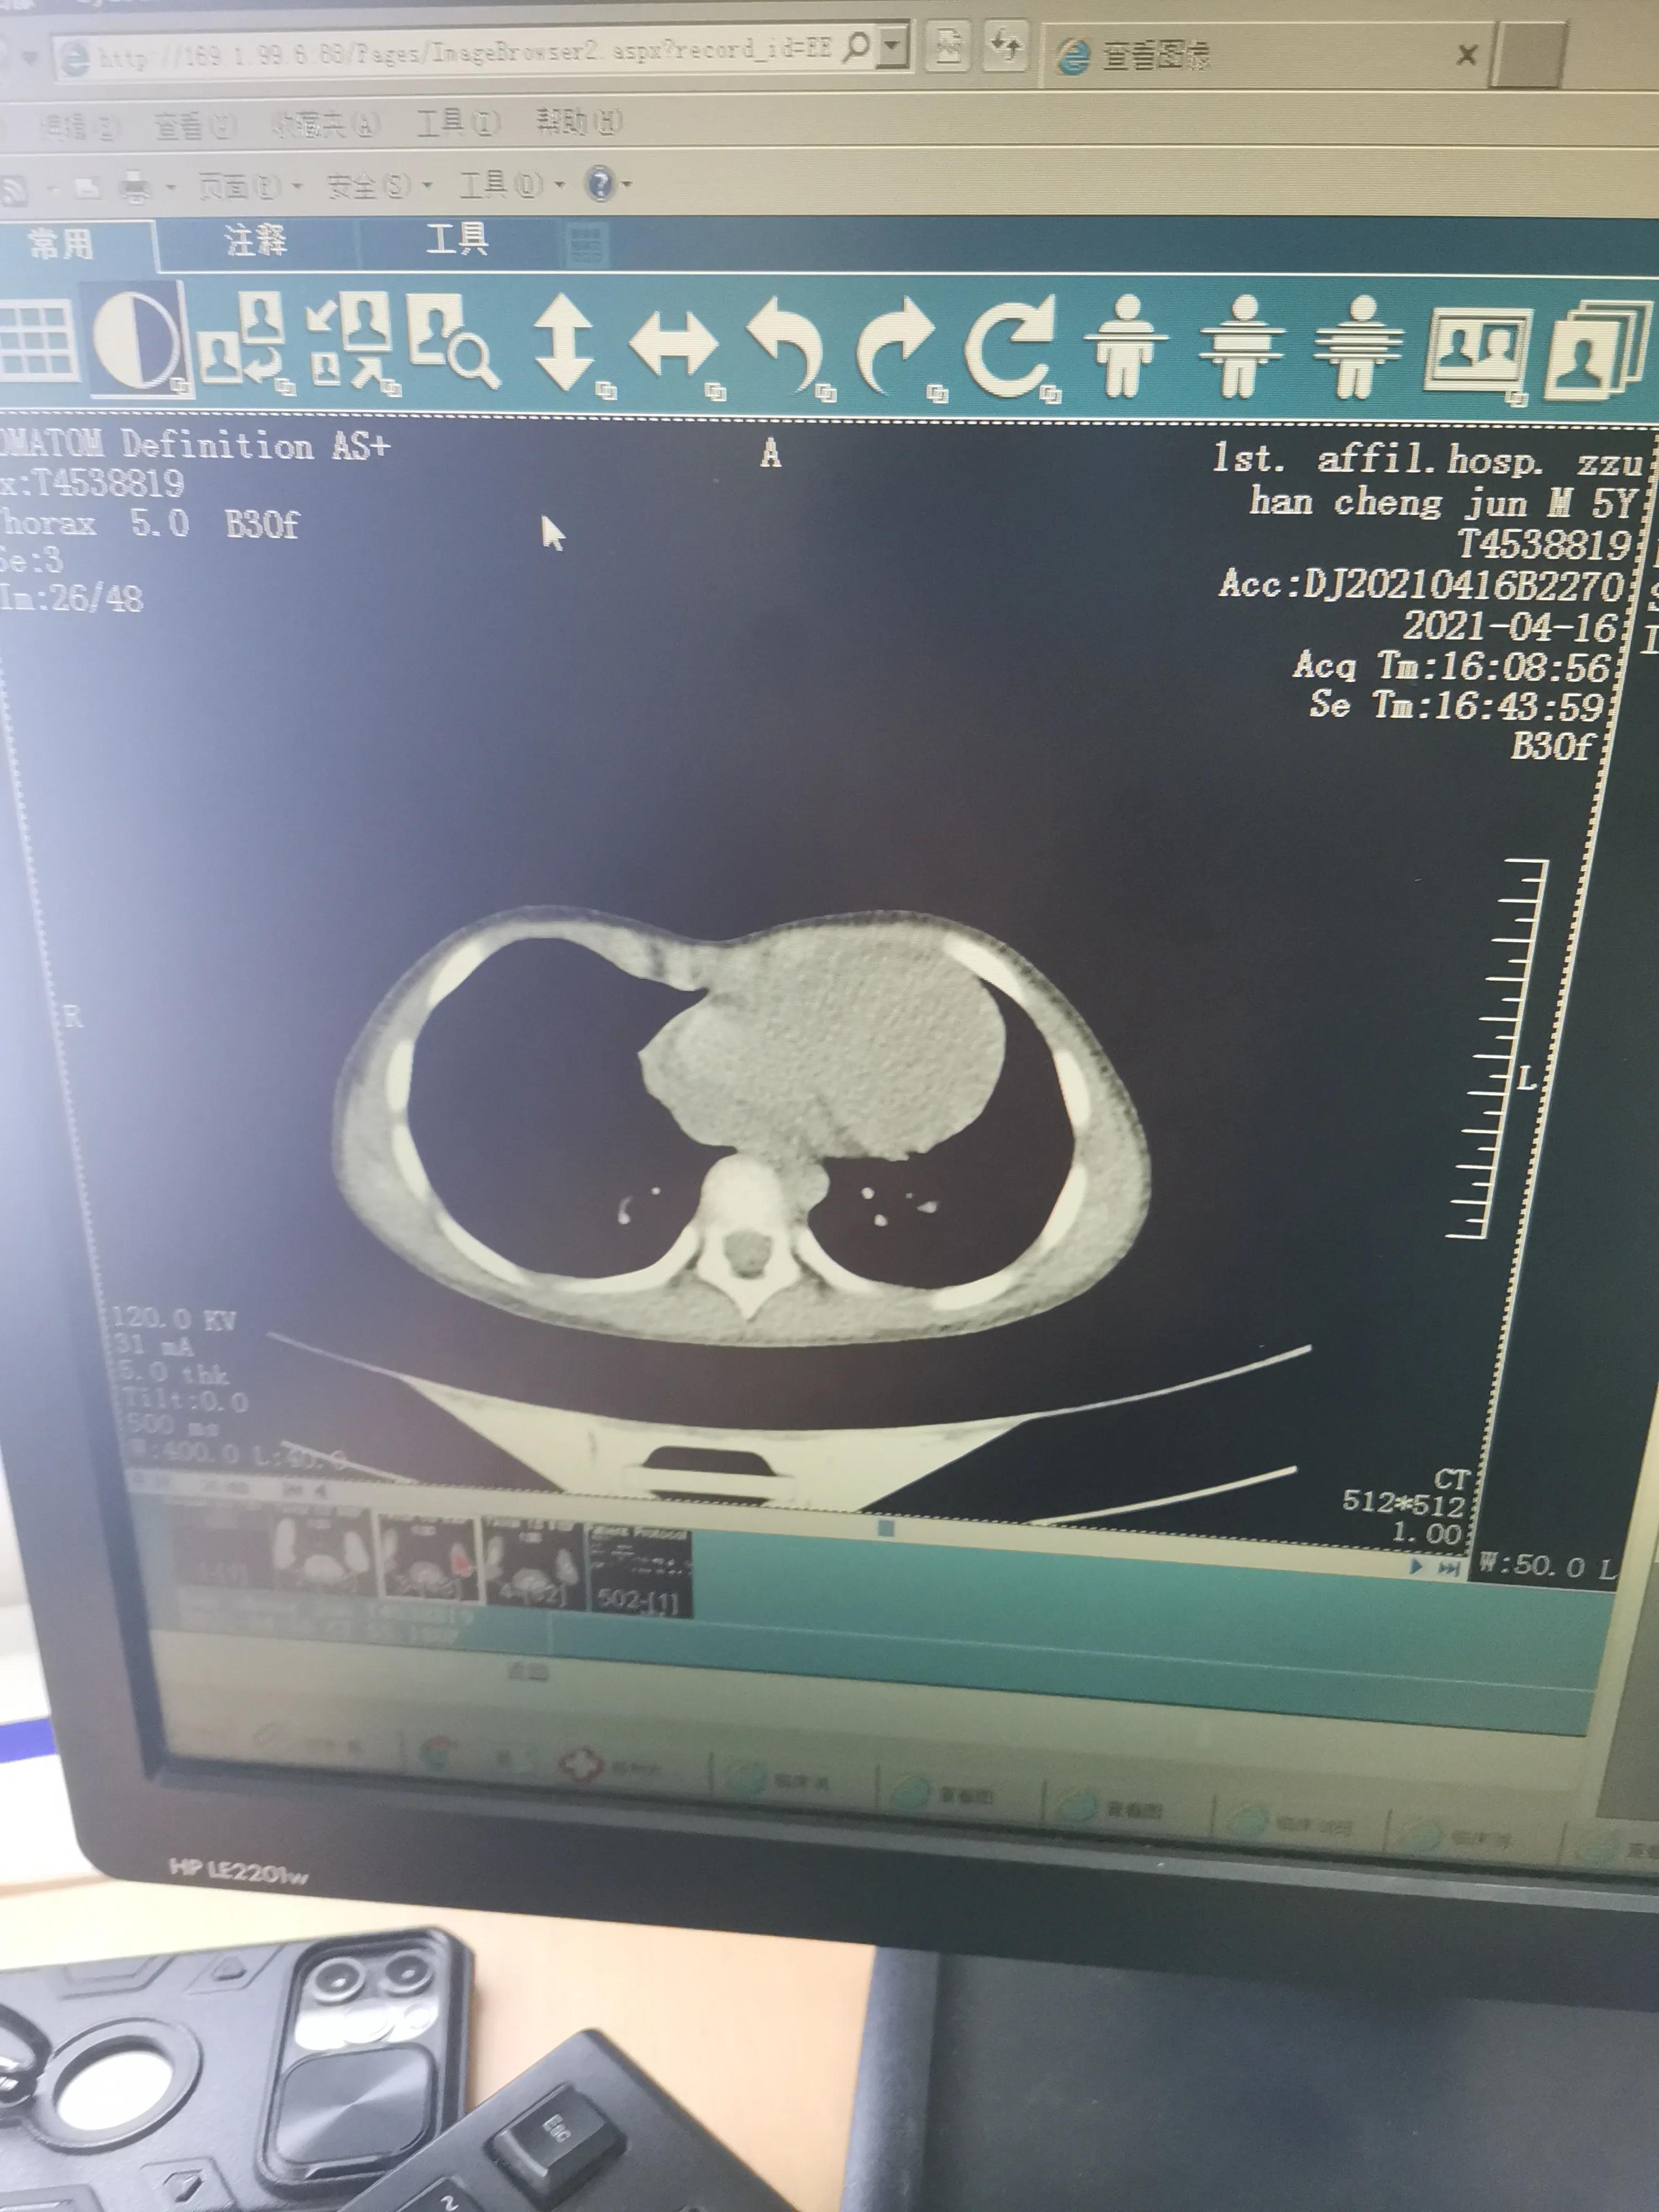

这是当时拍的CT,医生在讲解的时候我拍的照片

随着年龄的增长,到了一岁多的时候,胸前那个凹陷没有长平的迹象,我开始着急,带他四处去看,有医生说是佝偻病,最后来到郑州儿童医院,医生说这是漏斗胸,但是现在孩子还太小,有的漏斗胸可以自愈,加强锻炼,也有恢复的可能。我们也是抱着乐观的心态,想着积极给娃娃补钙,说不定长着长着就好了,就这样,我们也都没有再纠结这件事。 2021年,程程已经六岁了,胸前的凹陷从外观上看,似乎没有那么严重了,除了在深呼吸和哭闹的时候,我们一度认为孩子往好的方向发展了。虽然脱了衣服有点难看,但孩子剧烈运动也没有影响,那就这样吧,没什么大碍。就是孩子特别瘦,和别的孩子站到一块,总是没有别的孩子昂首挺胸,感觉畏畏缩缩的,总是爱往沙发旁的地上坐,缩着腰,看到这,我总是忍不住要凶他,让他坐起来。孩子在参加别的活动的时候也没有自信,眼神永往妈妈这边看,有时我都选择走开,不看他,觉得孩子也挺可怜,我们也没有把他这些表现往他的漏斗胸上去想。 2021年4月,我们带着孩子去郑大一附院探病,顺带给程程检查检查,医生一看,建议做个ct,本以为就是常规检查,也没放心上,结果出来,却显示心脏前缘已经局部受压,看上去心脏已经变成了扁扁的,这下,我们开始慌了,医生算了下指数,程程的已经达到了3.8,属于重度症状,要进行手术治疗,没有自愈可能,还会随着年龄的增长,越来越严重,一块大石头压在了我们的心里,接下来怎么办?手术吗?孩子还小,手术创伤他能受得了吗?